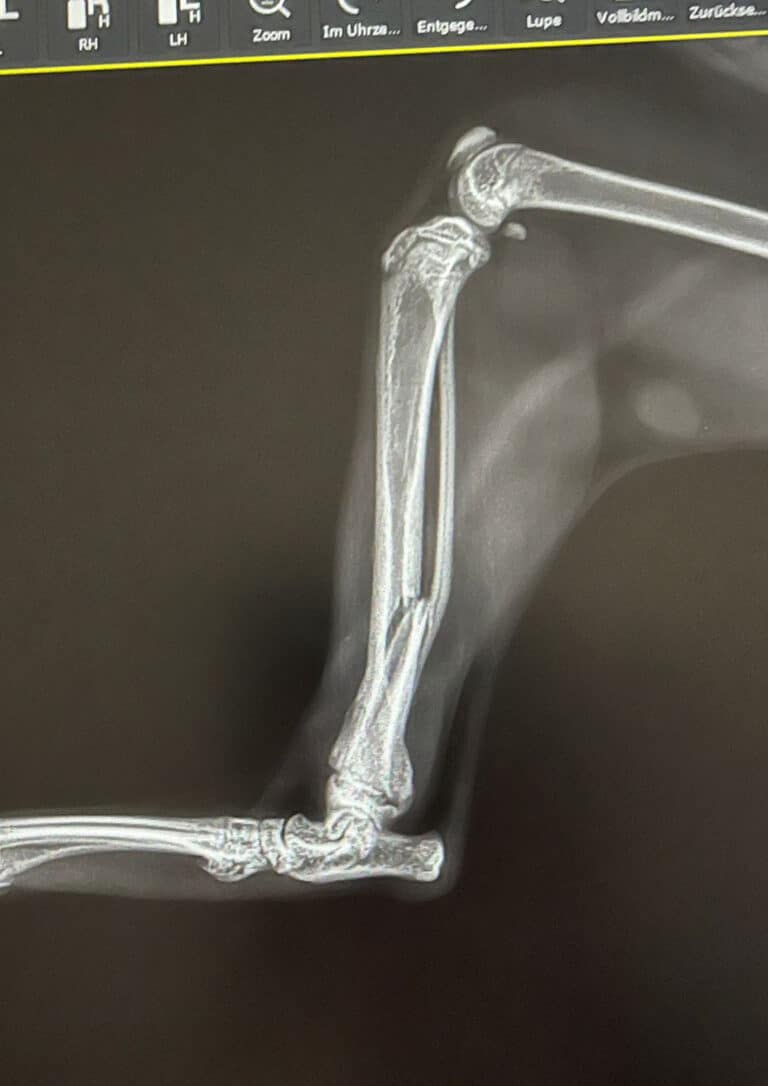

Als Mona zu uns kam, bemerkten wir sofort, dass sie sich kaum bewegen wollte. Jeder Schritt fiel ihr schwer. Beim genauen Hinsehen folgte dann die erschütternde Entdeckung: Mona leidet an einer unbehandelten Fraktur am rechten Hinterbein.

In der Tierklinik bestätigte sich schließlich die Diagnose: Nur eine Operation kann Monas Bein retten.